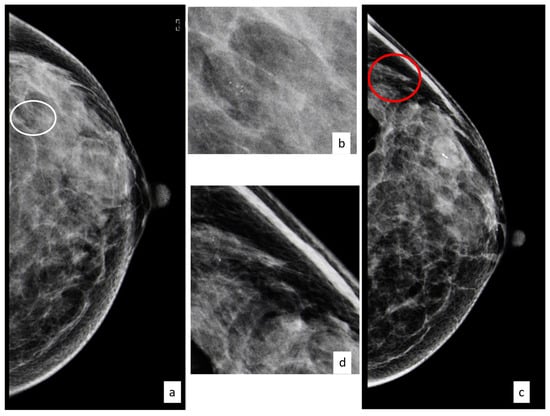

Out of 731 women, a total of 67 (9.2%) developed a subsequent cancer in the homolateral or contralateral breast in the follow-up period. Figure 1 shows the clinical case of a patient with a diagnosis of a B3 lesion that developed a subsequent carcinoma in situ after 3 years.

Figure 1.

Forty-nine-year-old patient with a cluster of microcalcifications at the upper outer quadrant of the left breast ((a) CC left view, with the white circle showing microcalcifications; (b) magnifications); the woman underwent vacuum-assisted excision and after three years developed a new cluster of microcalcifications ((c) CC left view, with the red circle showing microcalcifications; (d) magnifications) that, after biopsy, turned out to be ductal carcinoma in situ.

Figure 2 shows the case of a B3 lesion in the right breast of a patient who developed an invasive breast cancer in the contralateral breast after 5 years.

Figure 2.

A 56-year-old patient with a cluster of microcalcifications at the upper outer quadrant of the right breast that was diagnosed as ADH after biopsy ((a) MLO bilateral view, with the red circle showing microcalcifications corresponding to a B3 lesion; the red square shows a magnification of this area); the woman underwent surgical excision and after five years developed an architectural distortion in the contralateral breast ((b) MLO bilateral view, with the red circle showing distortion; the red square shows a magnification of this area) that, after biopsy, turned out to be invasive ductal carcinoma.